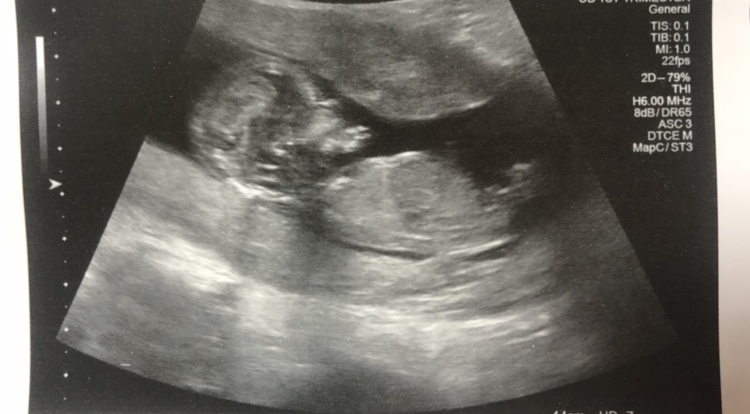

Please guess :) ultrasound 13 weeks 3 daysAttachment 40680